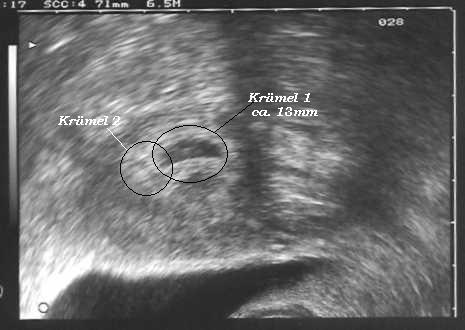

ich bin ganz aufgeregt, wir kommen gerade vom US beim Prof. er hat eine Fruchthöle gesehen mit Inhalt, er meinte er sieht den Dottersack und die entwicklung wäre gut (Zeitgemäß). Stellt Euch vor er hat noch eine 2. Fruchthöhle gesehen, die ist etwas kleiner konnte aber nicht sagen ob da auch was drin ist. Vieleicht bekommen wir ja doch 2 Ich kann es garnicht glauben, es wäre so schön. Wobei ich schon Angst vor einer Zwillingsschwangerschaft habe, weil da doch mehr pasieren kann, bzw. die Babys meisten früher kommen.

Den nächsten US habe ich am 16.07. um 11:00 Uhr mal sehen was man da sehen kann, kann es kaum abwarten. Ich habe Ihn auch gefragt ob ich so lange mein Gyn. Urlaub hat zu Ihm kommen darf da meine er kein Problem. Das finde ich richtig Klasse.

(8+4) alles super, Krümel ist 19 mm groß

(10+2) alles super, Krümel ist 3,5 cm groß

US 16.07.07 2 Herzlein schlagen Zwillinge